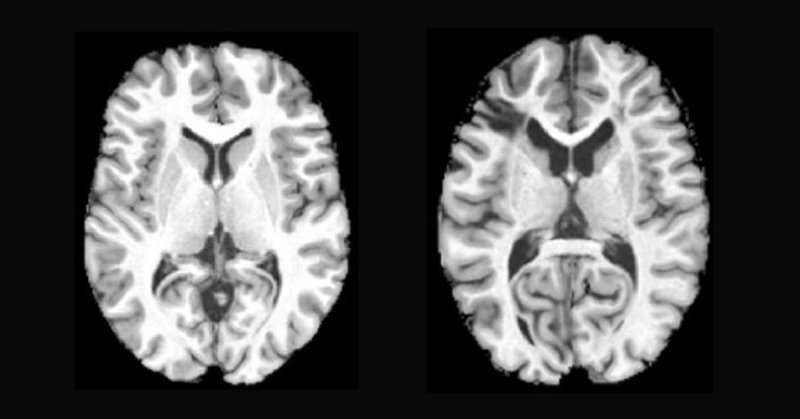

A new study shows that individuals living with sickle cell disease exhibit brain aging 14 years earlier than their actual age, even without stroke history, and socioeconomic factors also contribute. Read more here. https://t.co/wCymPbKxQw #NeglectedNoMore

Study also finds socioeconomic status linked to brain health in adults